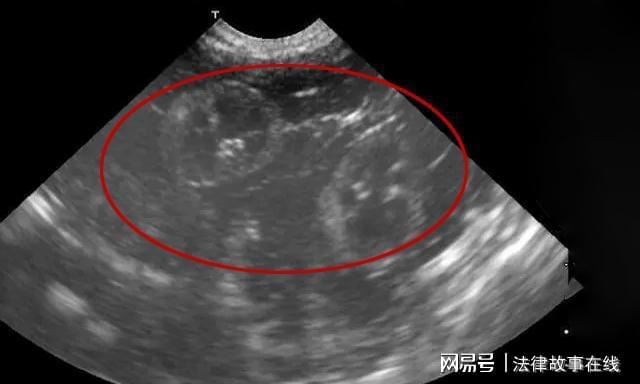

到了晚上,警方收到了法医传来的尸检报告,蔡某是因为脖颈处的大动脉破裂导致的失血性死亡,并且发现蔡某已经怀了3个月的身孕。

这一条报告令警方很是惊讶,根据蔡某的资料显示,蔡某时年已经53岁,在这个年龄已经很难受孕了。

在案发的前一天,贾某发现了母亲的抽屉里有一张B超,上面显示蔡某已经怀孕了三个月。

蔡某告诉贾某,肚子里的孩子是她的公公的孩子,所以他们要成为“一家人”了。贾某知晓后瘫坐在地上,待有了力气之后就与母亲发生了争执。